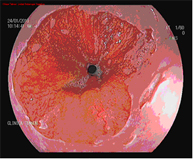

El diagnóstico se lleva a cabo mediante endoscopios de alta resolución con magnificación (aumento de la imagen), utilizando técnicas de cromoendoscopia añadidas, realizadas por endoscopistas especialistas en el diagnóstico precoz de lesiones precancerosas y la realización de biopsias que son analizadas.

Mucosectomía endoscópica

La mucosectomía consiste en la resección por vía endoscópica de una sección de la mucosa y submucosa (en este caso esofágica). Esta indicada siempre que en la endoscopia diagnóstica se aprecien lesiones sobreelevadas en el esófago de Barrett.